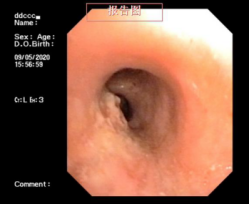

近日,一位患支氣管腫瘤患者到我院呼吸內科治療,檢查時,其腫瘤幾乎已經完全堵塞氣管管腔,若不及時手術,隨時可能發生呼吸衰竭。

情況危急,醫生立即為其抽取動脈血化驗并給予高流量吸氧等,但患者呼吸困難的癥狀緩解不明顯,必須及時將腫瘤切除。“如果按照傳統的手術方式,需將患者氣管切開,組織損傷性高、流血量多。由于患者腫瘤貼近降主動脈,切除過程中將伴有大出血的風險。”劉碧翠說,隨著我院內鏡技術的發展,對于這樣的重癥患者,可以利用呼吸內鏡迅速切除腫瘤,清理氣道內局部的壞死組織、分泌物并予以止血處理。

科室介入團隊經過精心準備后,立刻為患者實施內鏡介入手術,將氣道內腫物切除干凈。手術僅用時2小時,患者沒有發生大出血,很快便恢復出院。此次手術的成功開展,充分體現了呼吸內科對此類疑難危重氣道疾病患者的救治能力。